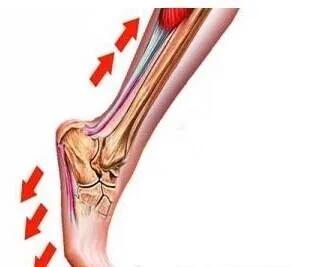

足跟是跟腱与跖筋膜的中转驿站,也是小腿向足部力学传导的枢纽(图2),足底跖腱膜是足底维持正常足弓、缓冲震荡、加强弹跳力作用的腱性组织。一般成人行走每天8000到10000步,而长期、慢性、轻微的累积伤,如果无法得到完全修复,就会造成足跟部腱骨连接部的慢性炎症,可以引起足跟部的疼痛,实质上就是足部跖筋膜纤维的断裂和其修复的反复过程(图3)。长时间的行走、过度的负重,会引起跖腱膜的劳损,导致局部无菌性炎症(图3),从而出现疼痛症状。后期,在足跟下方偏跖筋膜侧可有骨质增生,形成俗称的“骨刺”(图4,圈内)。

▲ 图2.足跟是跟腱与跖筋膜的力学传导枢纽

▲ 图3.足底跖筋膜炎